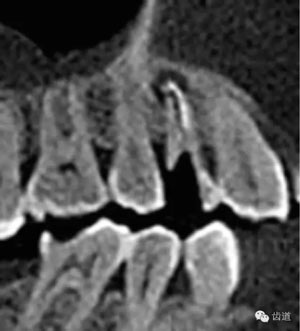

好的開始就是成功的一半。通過CBCT了解根管的位置,形態(tài),方向。

檢查顯示:近頰及腭根充填恰填,遠(yuǎn)頰根管內(nèi)有少許充填物影像。根尖明顯低密度影像。